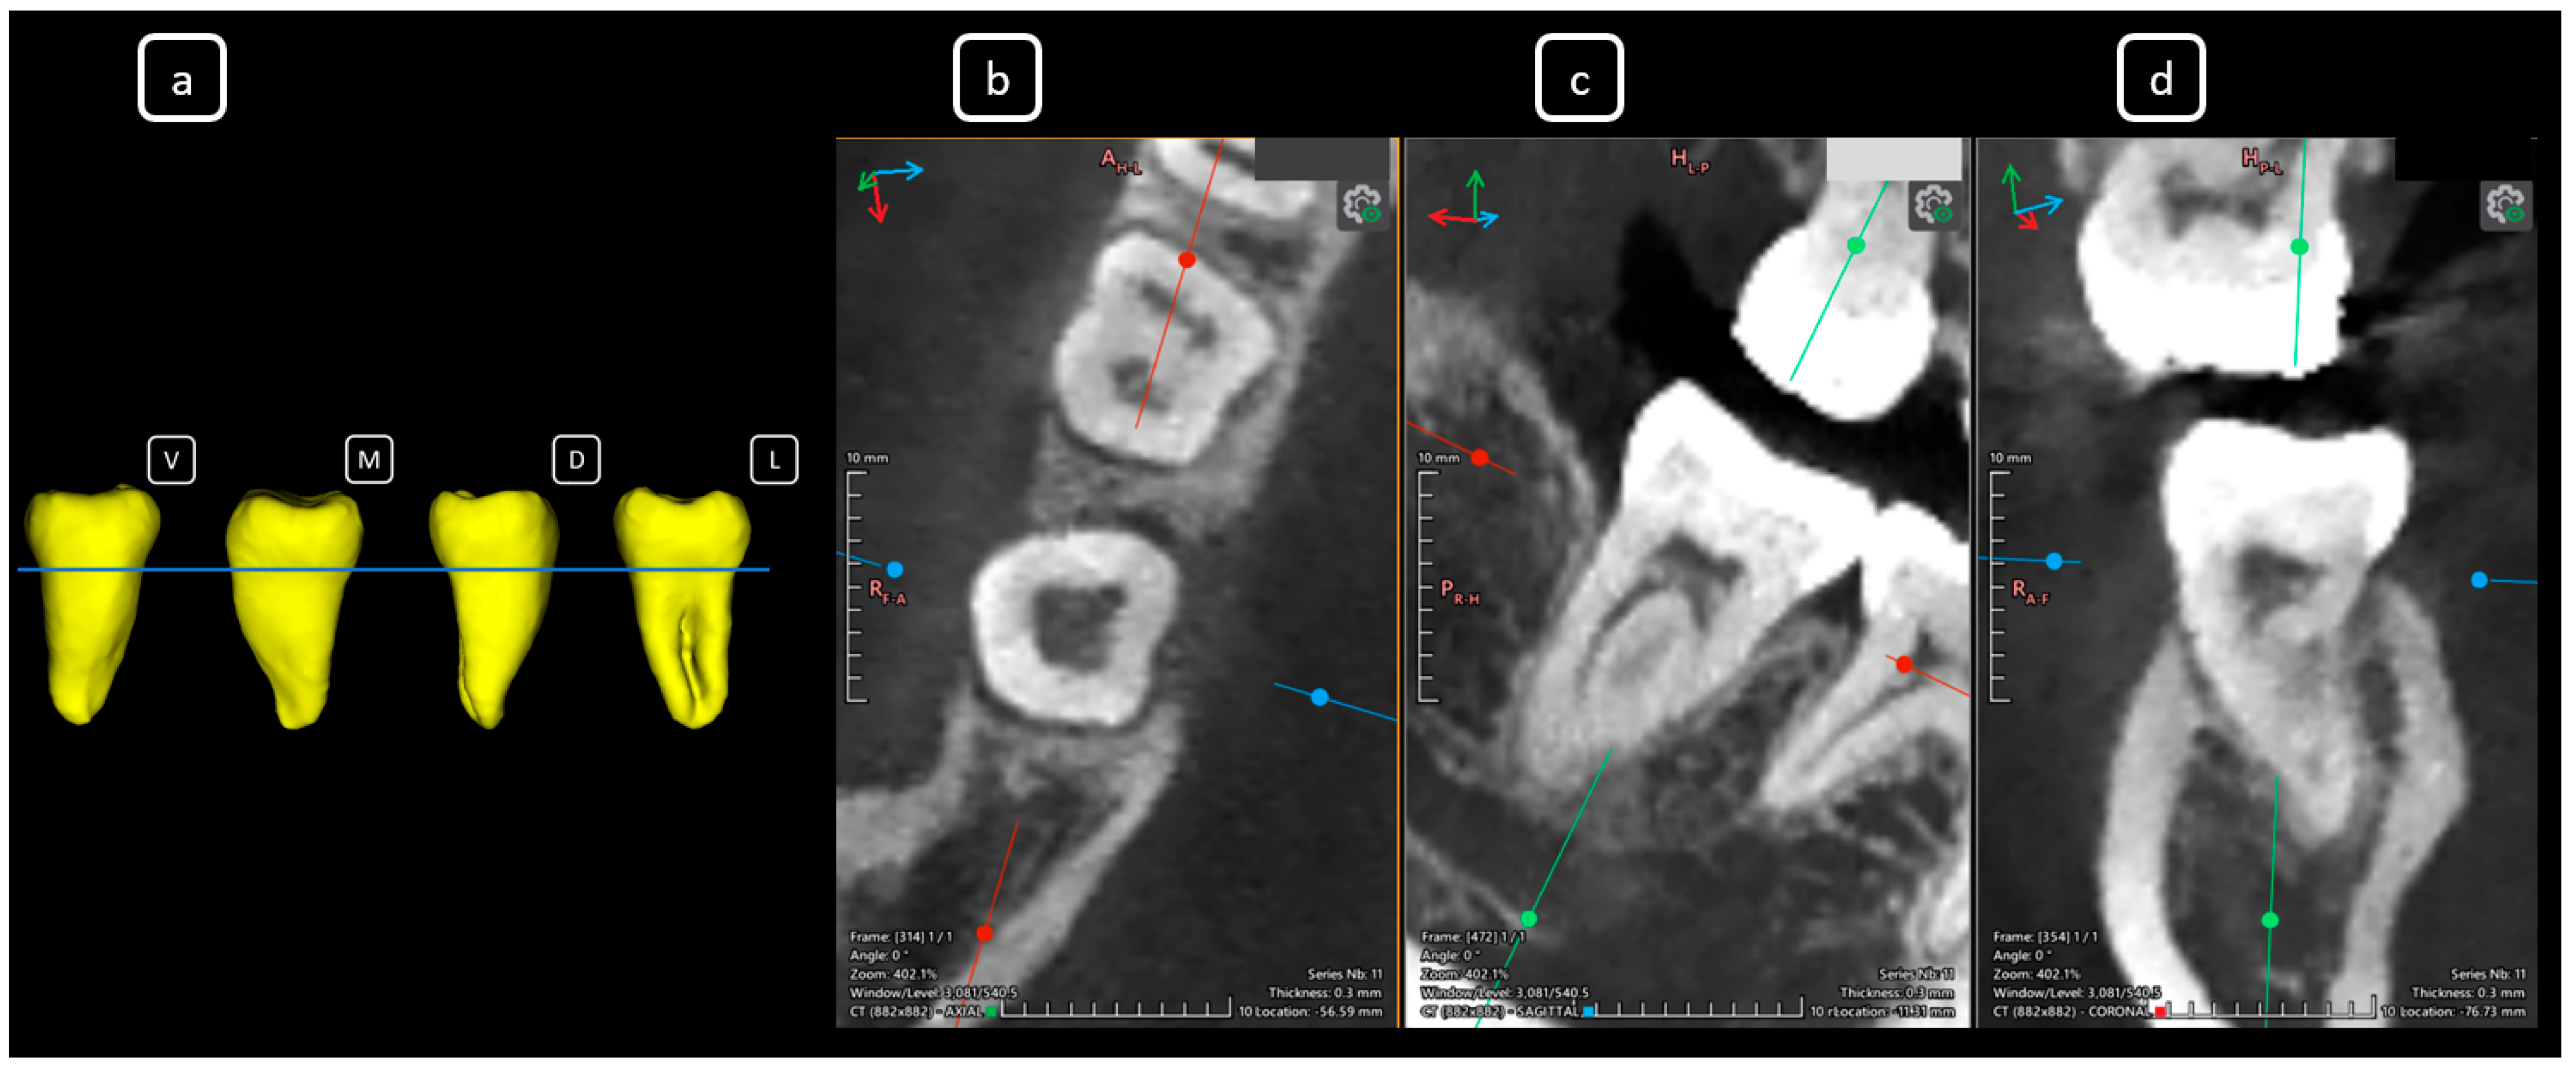

Imaging Findings of Clinical Significance in Endodontics During Cone Beam Computed Tomography Scanning of the Upper Airway—The Anterior, Bilateral, C-Shaped, Dual of Mandibular Root Canals: A Brief Case Report

García-Torres, E.; Guerrero-Falcón, D.L.G.; Bojórquez-Armenta, H.A.; Almeda-Ojeda, O.E.; Barajas-Pérez, V.H.; Solís-Martínez, L.J. Imaging Findings of Clinical Significance in Endodontics During Cone Beam Computed Tomography Scanning of the Upper Airway—The Anterior, Bilateral, C-Shaped, Dual of Mandibular Root Canals: A Brief Case Report. Diagnostics 2025, 15, 3157. https://doi.org/10.3390/diagnostics15243157